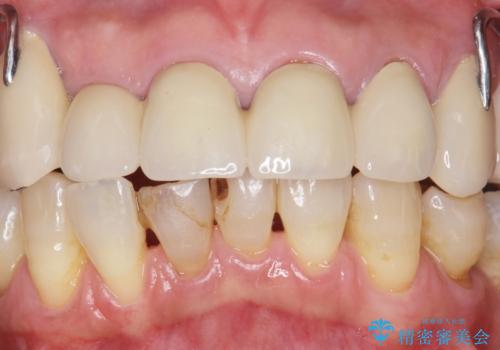

- 下の前歯が欠けてぐらぐらすることを主訴に来院された患者様です。

以前行った奥歯の治療により下顎前歯の動揺は改善傾向にあり顕著ではなかったのですが、欠けて黒くなっていることと少しの動揺が気になるとのことでした。

元気なうちに治療しておきたいという患者様の強いご希望により、下顎前歯の連結補綴と欠けている小臼歯の補綴治療を行いました。